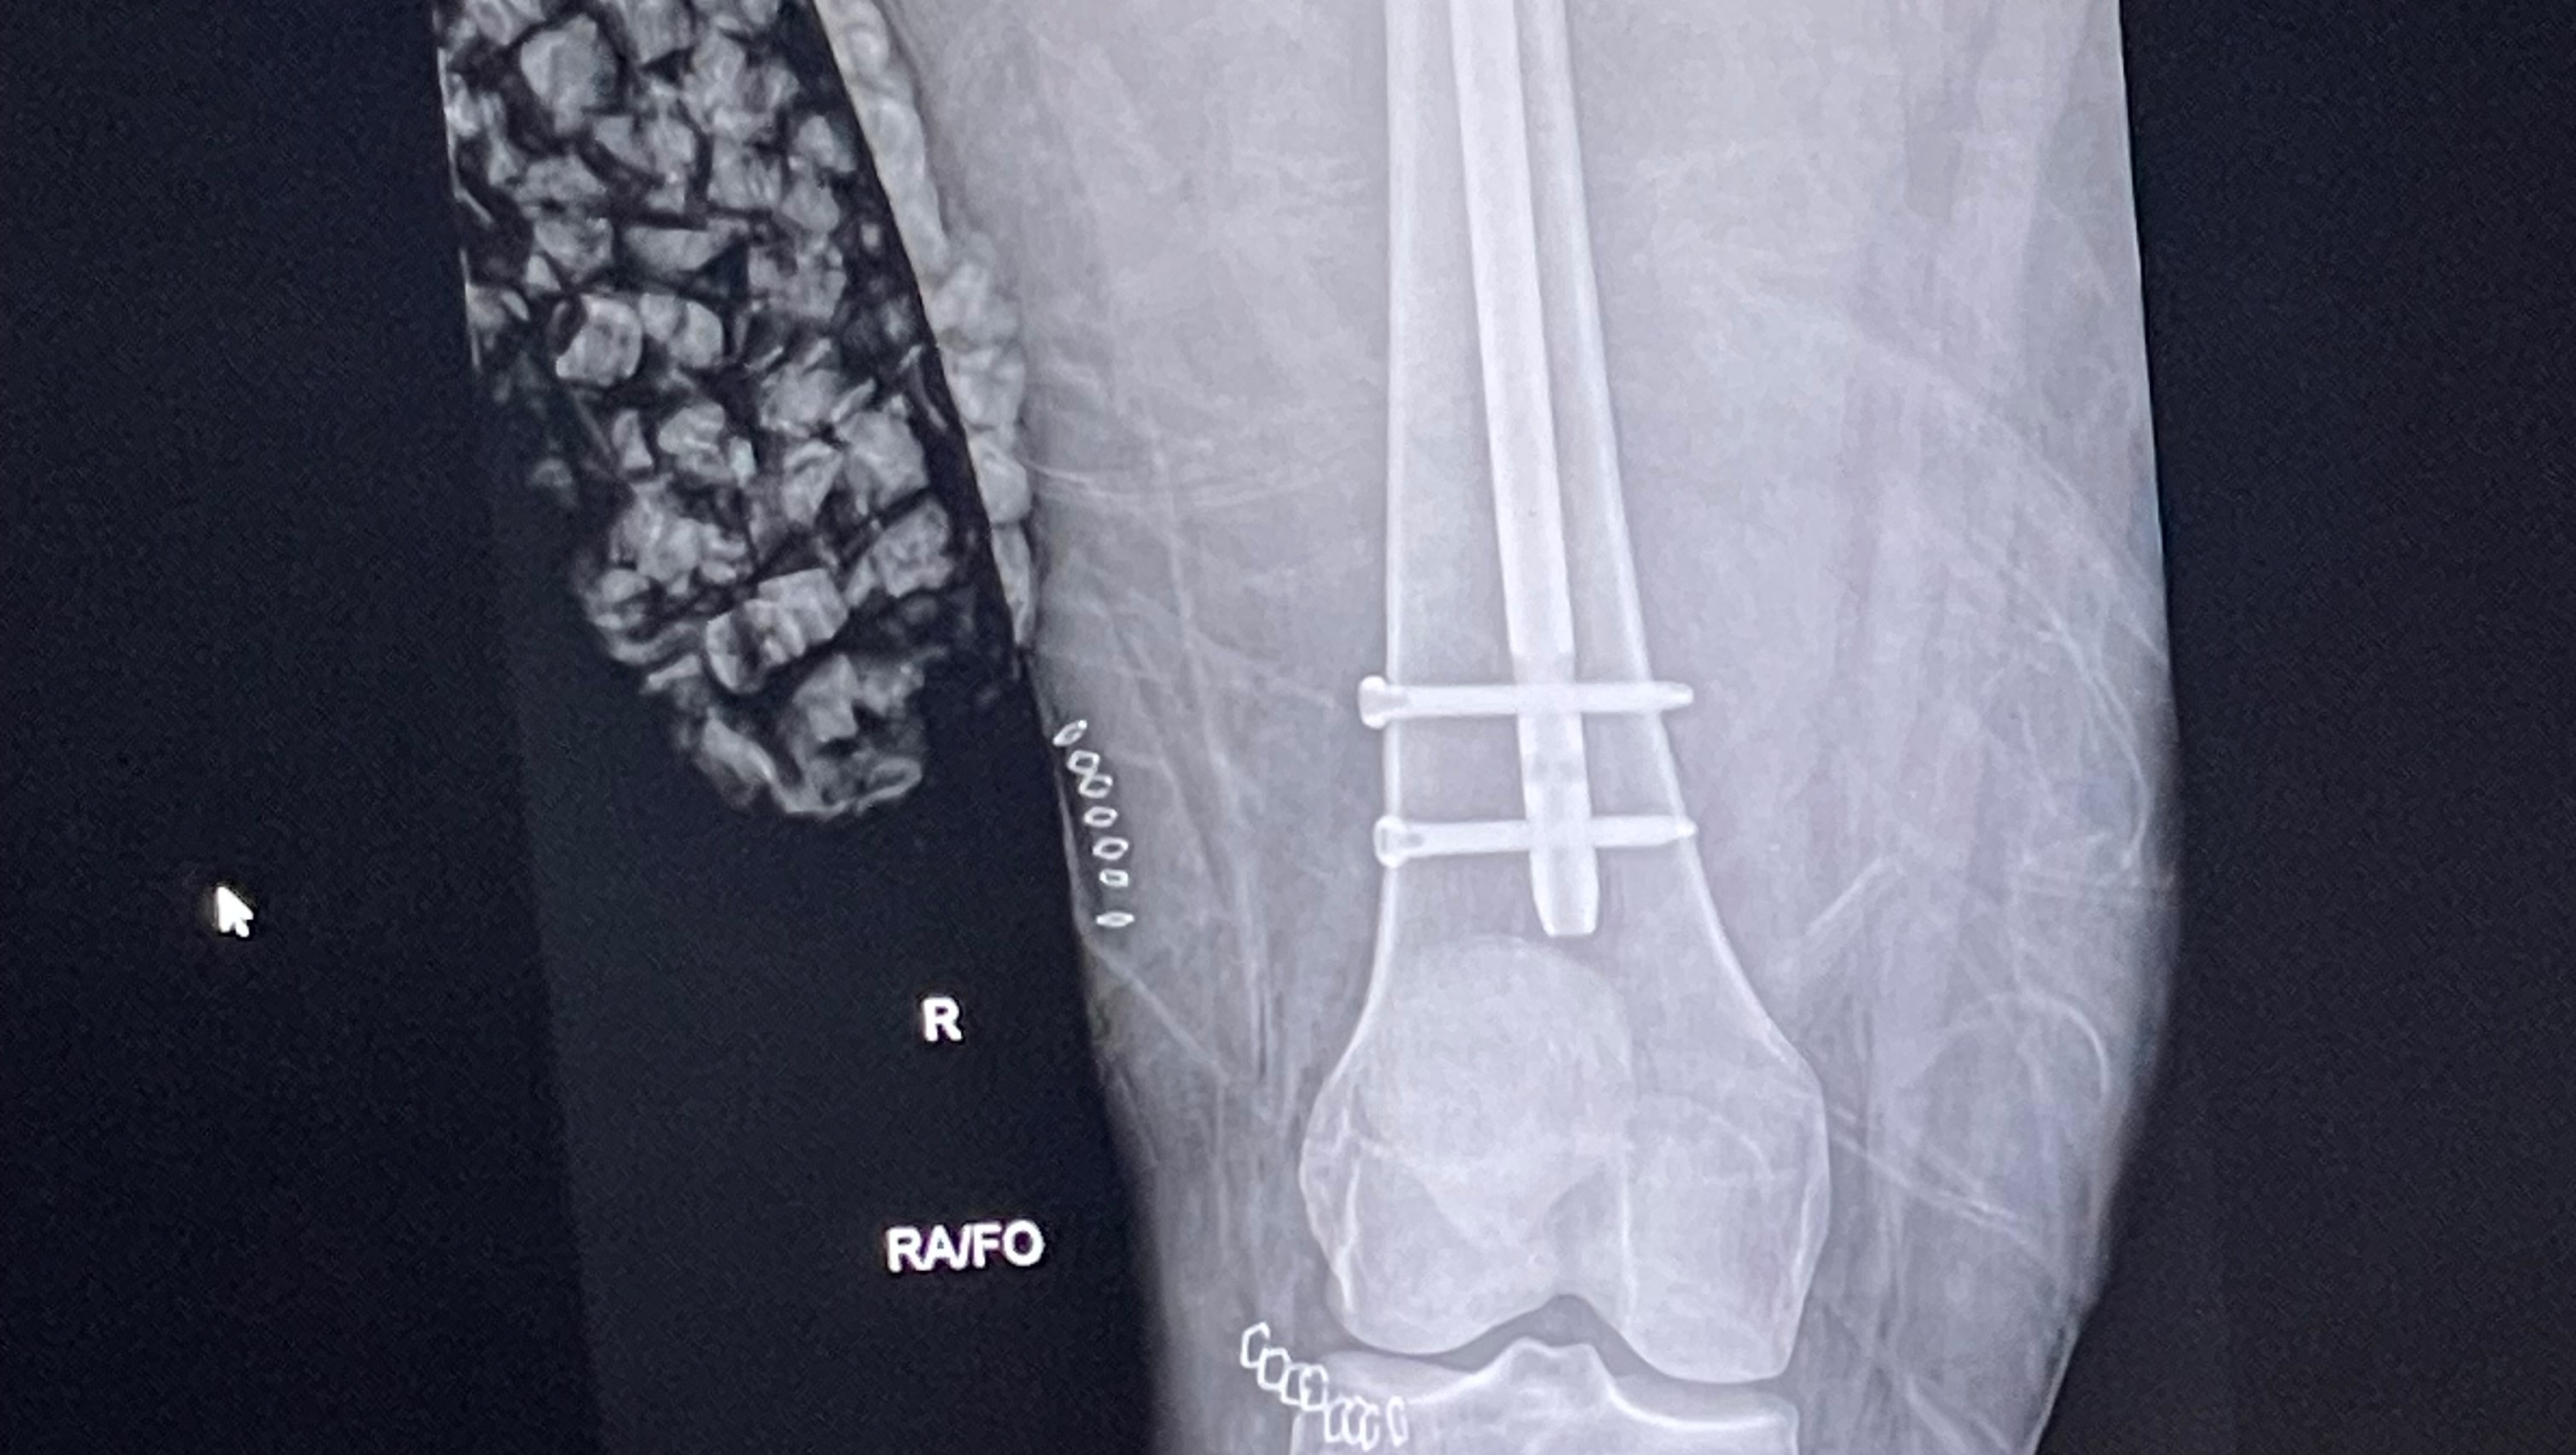

Hi, my name is Nesha Paige , and I’m a dedicated esthetician with a passion for helping others feel confident and beautiful in their own skin. Unfortunately, life took an unexpected turn when I was involved in a serious head-on collision car accident. While I’m grateful to be alive, the aftermath has left me with overwhelming financial challenges.

Due to my injuries, I’ve been unable to work, and the mounting medical bills, therapy costs, and loss of income have taken a significant toll. As an esthetician, my hands are my livelihood, and I’m now working hard to recover so I can return to doing what I love—helping my clients look and feel their best.